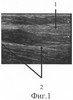

На фиг.10 представлена сонограмма больного П., 51 года, с застарелым повреждением локтевого нерва в средней трети правого предплечья (через 7 недель после начала дистракции).

Через 7 недель после начала дистракции (фиг.10) на месте дефекта выявлен регенерат локтевого нерва (фиг.10-1), заканчивающийся невромой, линейный размер которой составляет 4 мм (фиг.10-2), его дистальный фрагмент с патологическими изменениями на протяжении 5 мм (фиг.10-5). Диастаз между невромой и дистальным фрагментом стал равен 3 мм (фиг.10-5). Истинный диастаз фрагментов локтевого нерва сократился до 12 мм. Произведен заключительный этап операции, на котором данные ультрасонографии подтвердились и был выполнен эпиневральный шов локтевого нерва.